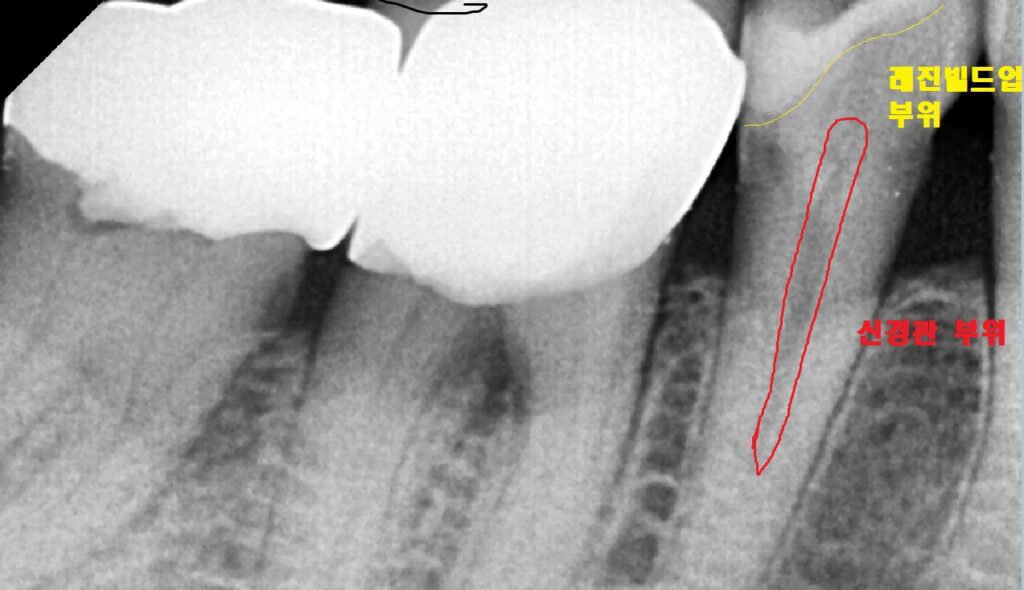

엑스레이 상에서도 볼때

빨간색의 신경관 부위에 아주 가까운 노란색

즉 빌드업 부위가 발견이 됩니다

매우 가깝기는 하지만 적합이 좋기 때문에

시린증상이나 통증은 없었습니다.